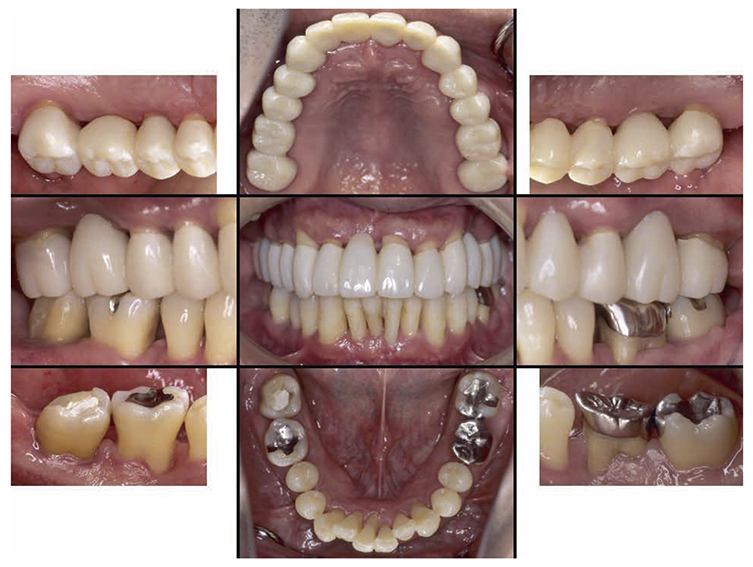

At the reevaluation examination after treatment to restore oral function, the color of gingiva was pink, and with prosthetics, intraoral harmony was replicated esthetically and functionally. (Fig.6a). The average PD across the entire jaw was 2.1mm, maximum PD was 4.0mm, the ratio of PD of 3mm or below was 99.3%, no BOP was found and the condition of the periodontal tissue was stable (Fig.6b). In the X-ray, continuity of the alveolar hard line was replicated and the sequence of bone trabeculae was normal, and therefore, the patient transitioned to the SPT phase (Fig.6c).

Fig 6a

(Fig.6a) Intraoral photo after completion of restoration of oral function was completed(2013.4)

Fig 6b

(Fig.6b) Reevaluation and examination after completion of restoration of oral function (April 2013)

Fig 6c

(Fig.6c) Digital X-ray 14 after completion of restoration of oral function (April 2013)